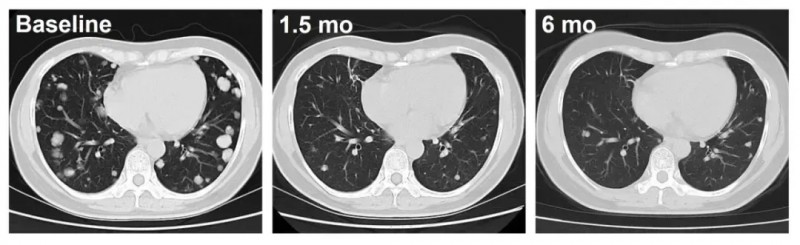

其中,剂量水平4组的C023号患者治疗效果尤为引人注目。接受C-CAR031治疗后,该患者的肿瘤呈现持续退缩的积极态势,仅治疗1.5个月时,肺部转移病灶便出现深度应答,影像学检查清晰显示肿瘤显著缩小,充分彰显了C-CAR031令人振奋的临床潜力。

▲图源“ASCO”,版权归原作者所有,如无意中侵犯了知识产权,请联系我们删除